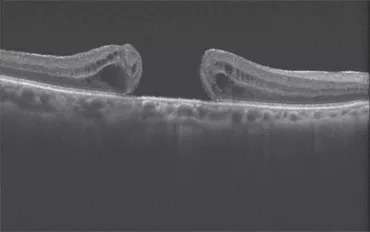

The macula is a small area in the center of the retina where light is sharply focused to produce the detailed color vision needed for tasks such as reading and driving. When a full-thickness defect develops in the macula, the condition is referred to as macular hole.